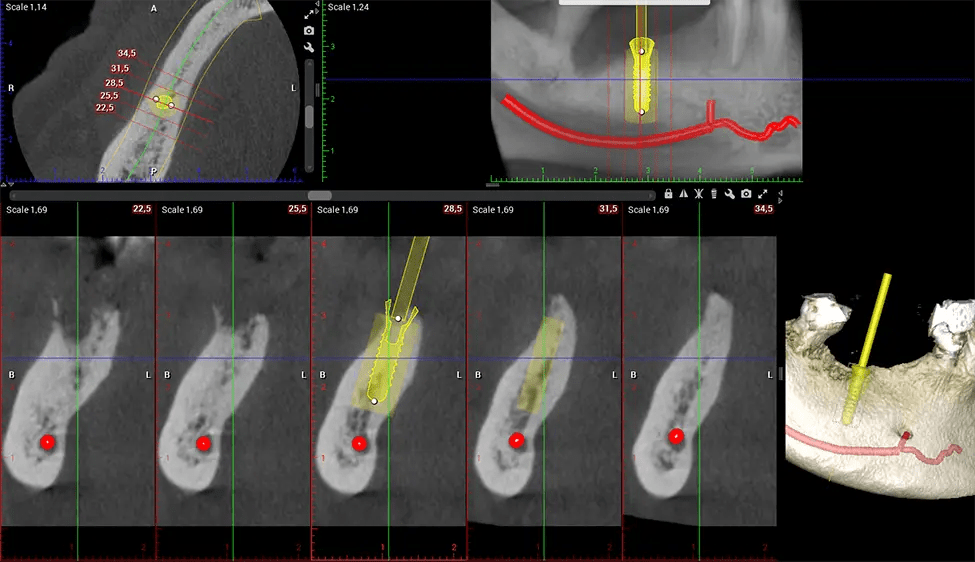

Cone Beam Computed Tomography (CBCT) is an advanced imaging technique used in dentistry and maxillofacial surgery to obtain detailed 3D images of the oral and maxillofacial structures. At Dr G Dental Studio, our CBCT scanners utilize a cone-shaped X-ray beam and a specialized detector to capture images from different angles. A computer then combines these images to create a 3D representation of the patient’s oral anatomy.

The patient is first positioned in the CBCT scanner, which typically consists of a rotating arm that houses the X-ray source and a detector. The patient’s head is immobilized to ensure accurate image capture. The X-ray source and detector rotate around the patient’s head, capturing various X-ray images from multiple angles. As the X-ray source rotates, it emits the cone-shaped X-ray beam towards the detector. The detector captures the X-ray images, which are then processed by the CBCT software.

After the scanning process, the captured X-ray images are processed by the CBCT software, which applies algorithms to reconstruct a detailed 3D image of the scanned area. The software compiles these individual X-ray images and creates a digital 3D representation of the patient’s anatomy. The reconstructed 3D CBCT image can be viewed and analyzed by the dentist or radiologist. This image can be manipulated, rotated, and zoomed in or out to examine specific structures and evaluate the patient’s condition.